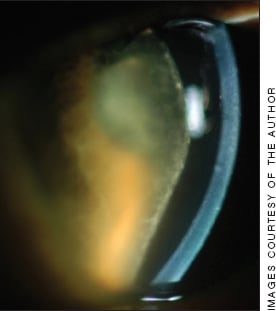

Figure 2. Achieving a durable remission of at least three months prior to surgery will diminish the likelihood of postoperative inflammation such as this.